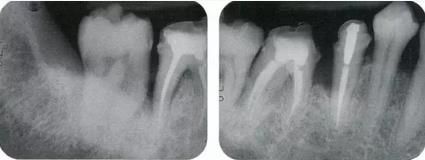

360截圖20170422102020512.jpg

▲圖11-1,2

▲圖11-1,2  術(shù)前的X光片、右下6,7之間存在牙根接近,并存在10mm的牙周袋。

360截圖20170422102030273.jpg

▲圖11-3,4

▲圖11-3,4 齦瓣剝離翻開的狀態(tài)。右下6的遠(yuǎn)中牙根有較深的骨組織缺失,右下7的頰側(cè)有II度根分叉病變和近遠(yuǎn)中側(cè)有垂直型骨組織缺失。

360截圖20170422102040585.jpg

▲圖11-5

右下6進行牙半切除并將遠(yuǎn)中牙根拔除。右下5,7的骨組織缺損部位進行骨組織移植,以及在右下7進行GTR(wraparound)。

360截圖20170422102053504.jpg

▲圖11-6,7

▲圖11-6 修復(fù)完全后6個月。

▲圖11-7 術(shù)后4年4個月。